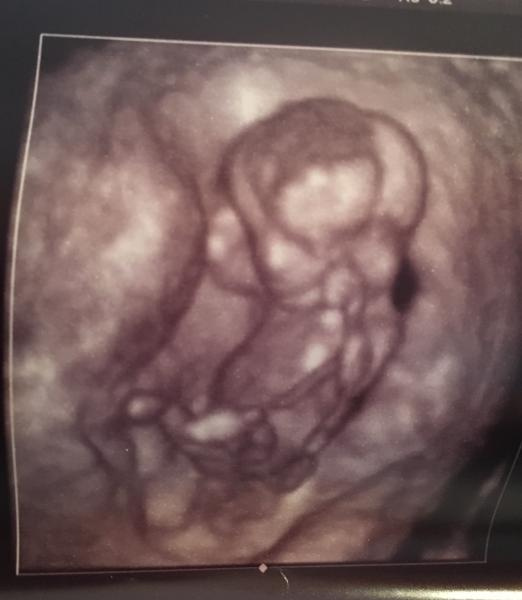

Min bebis är 6.1 cm lång, så härligt att få se den igen igår!!

Dock så gör det så ont när hon kollar(läkaren) så jag hade lite svårt att slappna av och kolla på bilden. Men min partner beskrev för mig och sa att bebis"vinkade" och sprattlade glatt.

Också intressant hur olika våra ultraljudsbilder kan se ut, i samma vecka.

Jag upplever att mångas bilder har man sett ett huvud och sen en mer "Bönformad" kropp...På min bild var det två bönor..haha

Men "dragen" blir ju tydligare längre fram.....Senast var bebis 4mm så det är så jävla coolt att det händer saker!